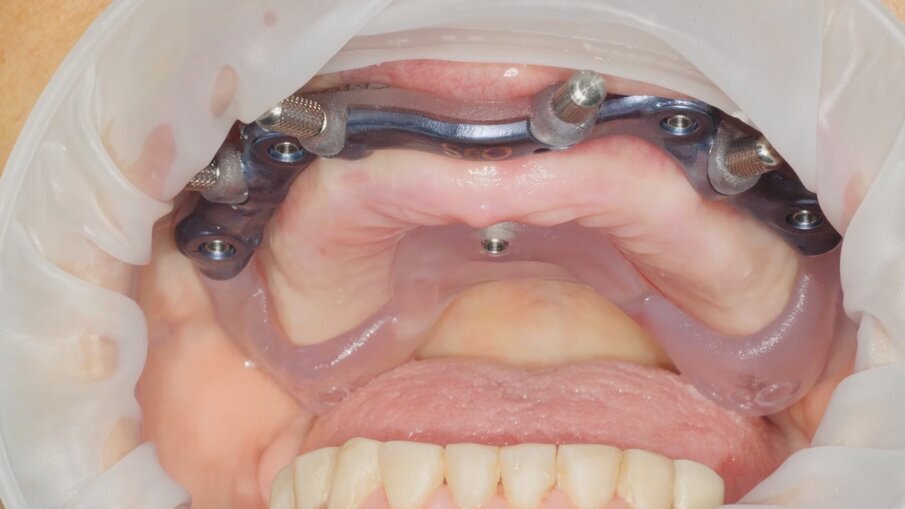

Nella fase di controllo finale possiamo apprezzare come i rapporti di intercuspidazione programmati siano stati perfettamente rispettati (Fig. 28), senza necessità di ricorrere a procedure di auto-centratura della protesi, grazie ad una attenta pianificazione digitale. Eseguiamo una scansione con scan abutment in posizione prima di procedere con la rimozione della dima base e il fissaggio della protesi (Figg. 29-31). Controlliamo le possibilità di mantenimento igienico tenendo conto che, trattandosi di un intervento flapless, non abbiamo le problematiche legate alla gestione di una linea di incisione (Fig. 32). La Fig. 33 mostra la corretta guarigione dei tessuti quindici giorni dopo il trattamento. Eseguiamo un controllo radiografico mirato a verificare il corretto alloggiamento di tutti gli impianti e della protesi (Fig. 33), dove possiamo vedere la struttura di rinforzo in fibra di vetro.

Fig. 29

Fig. 30

Fig. 31

Fig. 32